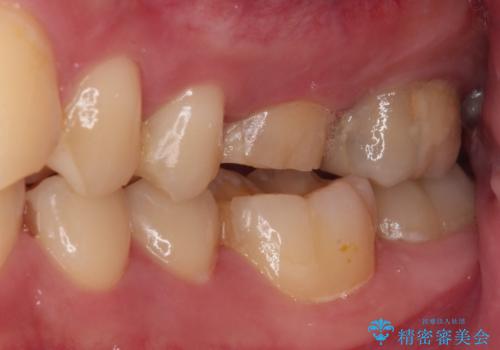

- 近医にて、虫歯が大きいため抜歯が必要と言われたとのことで来院された患者様です。

診査したところ、根尖部の病変は大きいものの、抜歯が必要とは決して思えず、まずは根管治療を行うべきと判断しました。

根管治療後、病変が消退したことを確認し、オールセラミッククラウンにて補綴治療を行うこととしました。